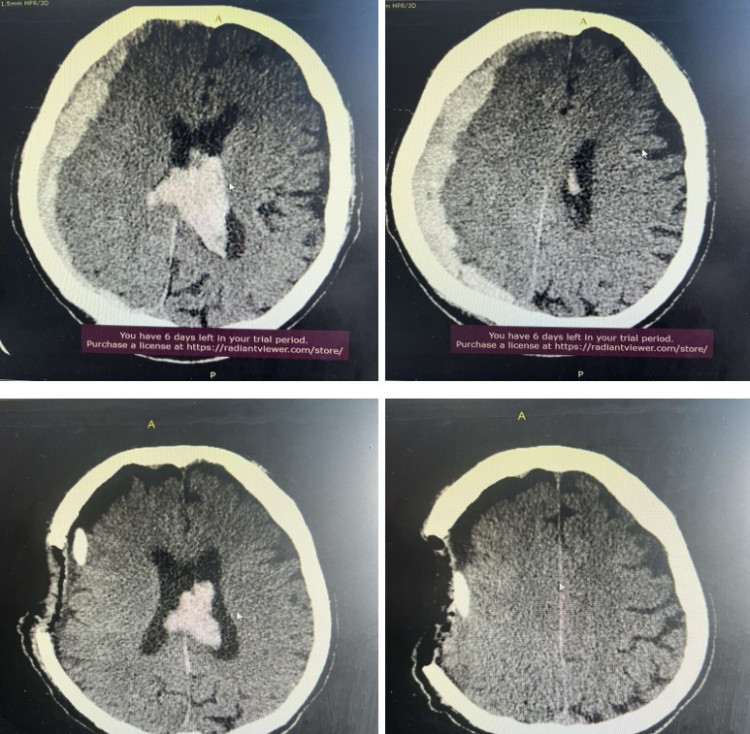

Гэмтэл согог судлалын үндэсний төвийн Толгойн мэс заслын тасгийн их эмч Д.Ган-Эрдэнэ, Мэс засал, мэдээгүйжүүлгийн нэгдсэн тасгийн сувилагч Ш.Мэндбаяр, жолооч Д.Энхжаргал нарын алсын дуудлагын баг Ховд аймагт ажиллаж, гавал тархины хүнд гэмтэлтэй өвчтөнд яаралтай тусламж үзүүллээ.

Тухайлбал, тус баг бүрэлдэхүүн Ховд аймгийн Бүсийн оношлогоо эмчилгээний төвийн гэмтлийн эмч Б.Батбулган, Б.Лхагвасүрэн болон мэдээгүйжүүлгийн эмч П.Балжинням, мэдээгүйжүүлгийн сувилагч Н.Ганчулуун, мэс заслын сувилагч Ц.Отгонжаргал нартай хамтран явганаас савж унан гэмтсэн 62 настай дээрх өвчтөнд яаралтай мэс засал эмчилгээ хийж, амь насыг нь аварсан байна. Өдгөө өвчтөний биеийн байдал тогтворжиж, Эрчимт эмчилгээний тасгаас шилжин эмийн эмчилгээ хийлгэж байгаа юм.